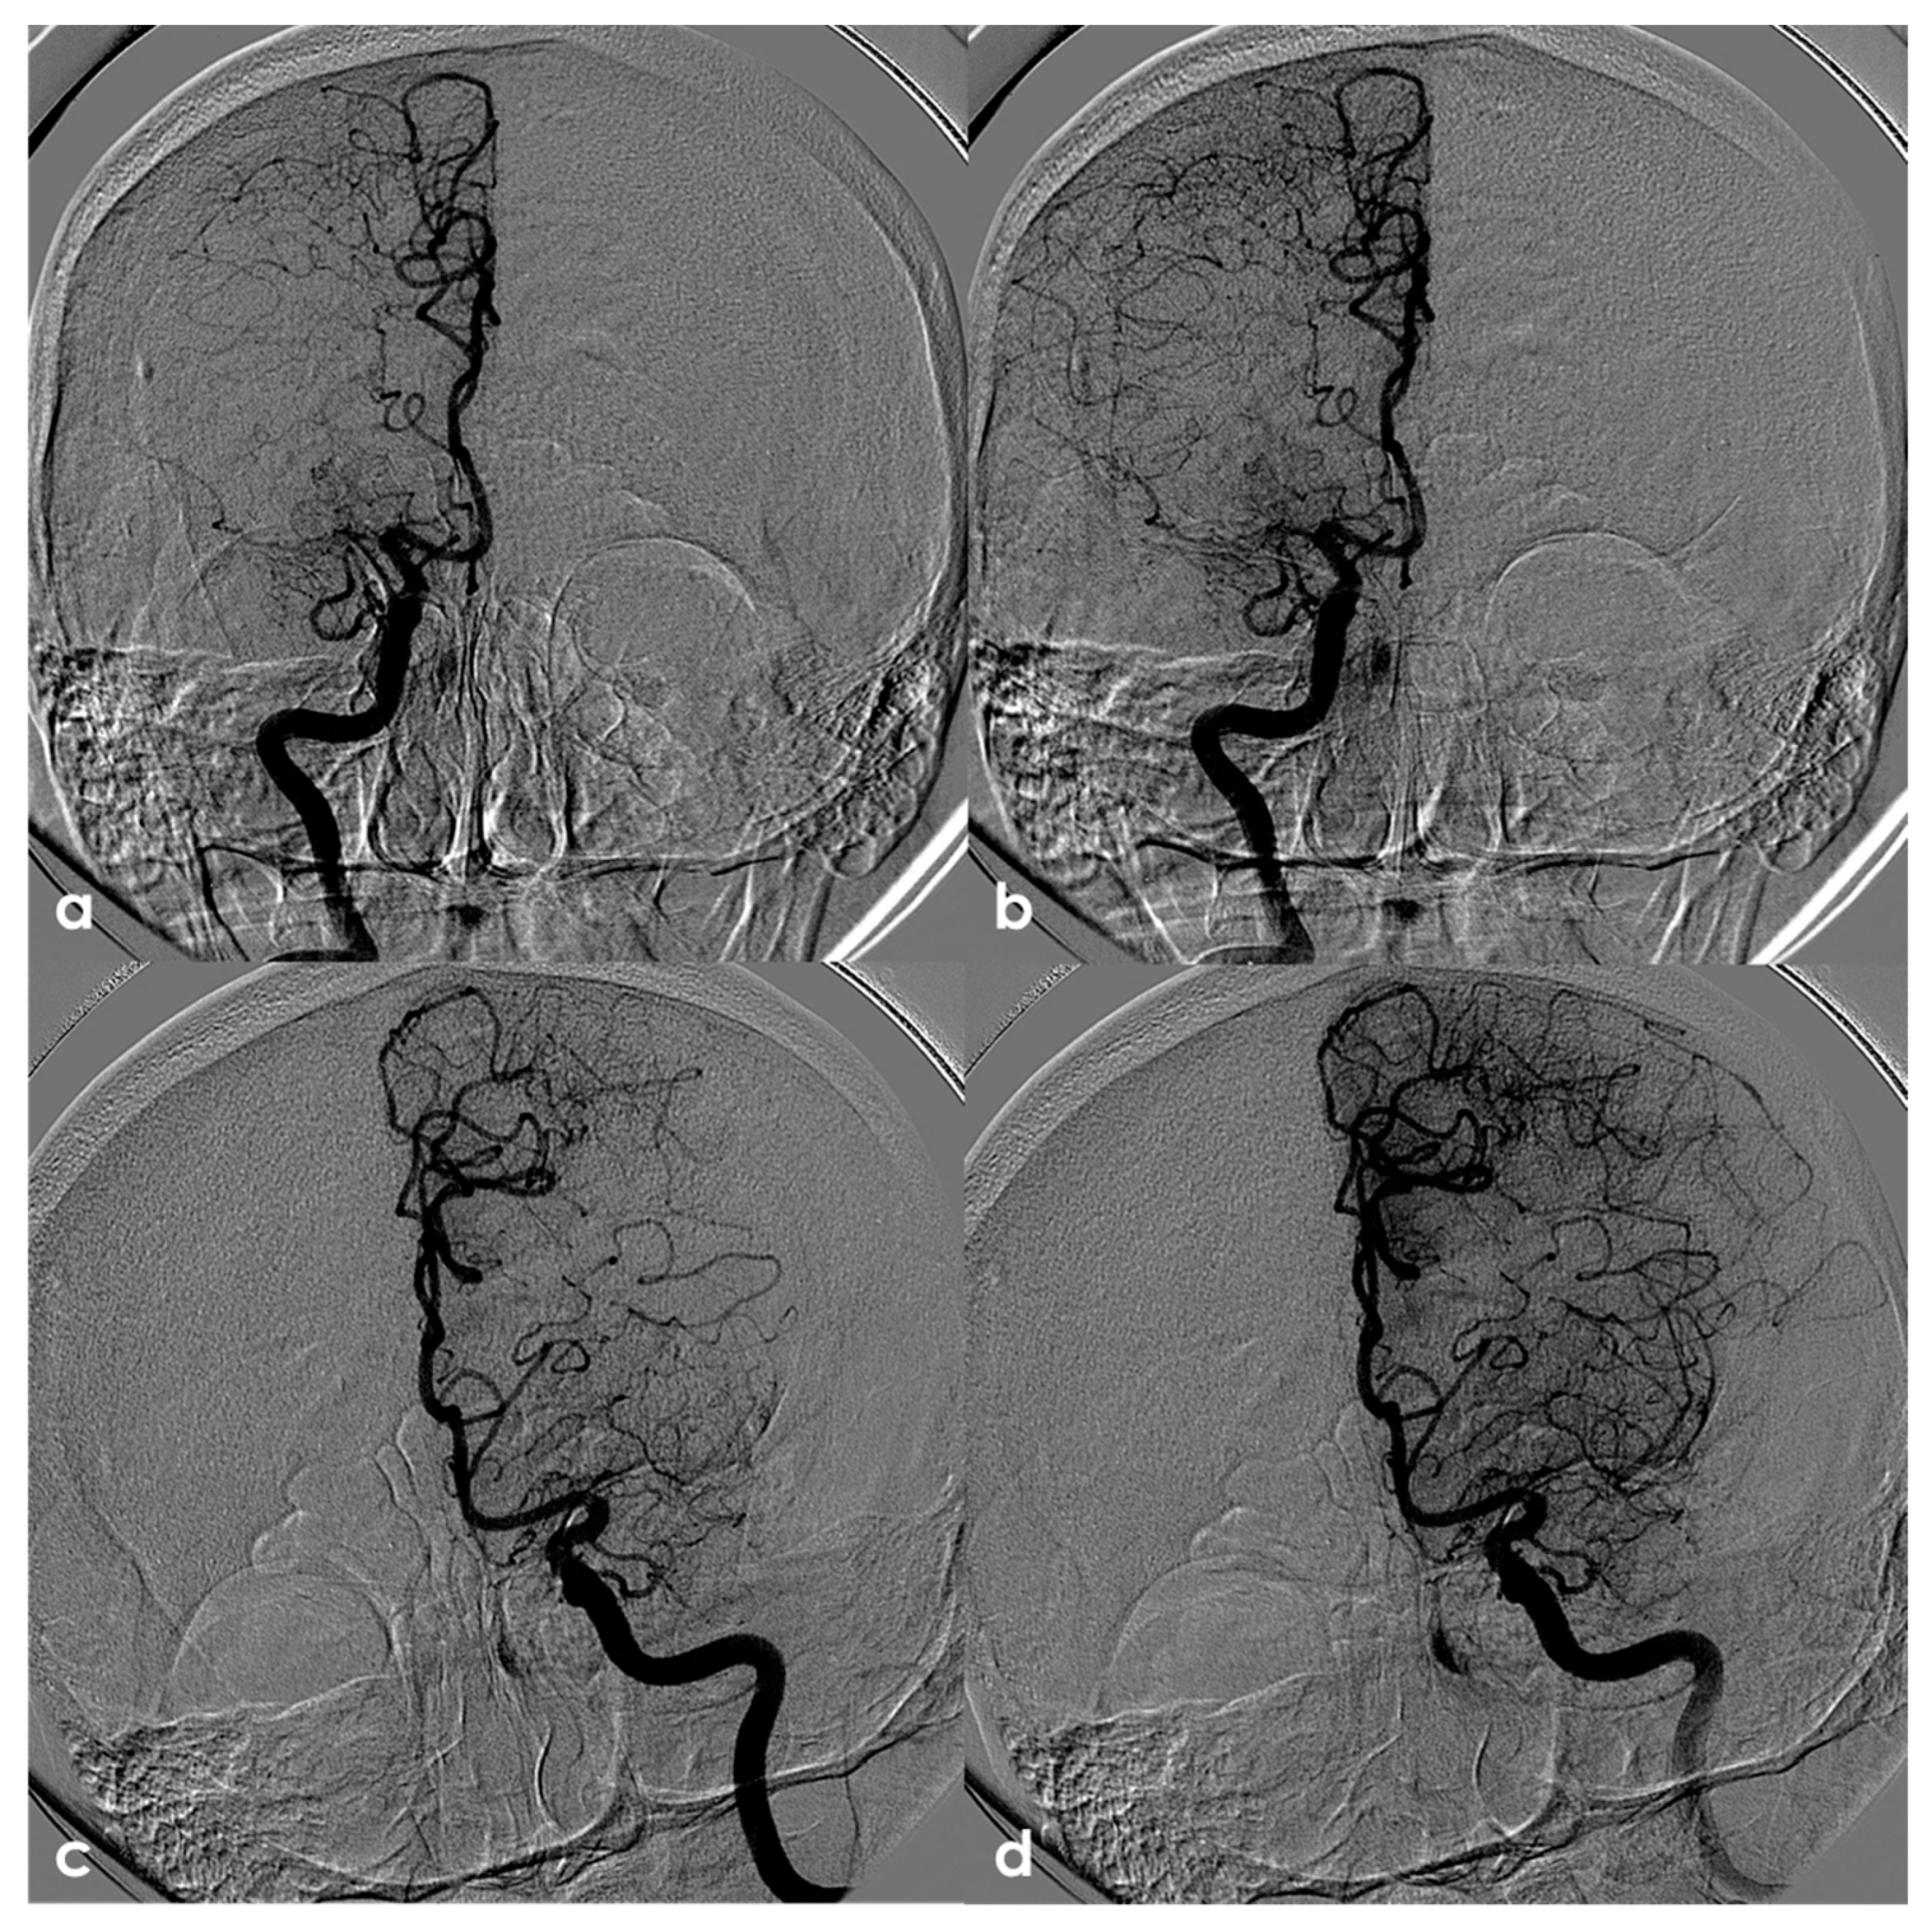

Figure 4.

Digital subtraction angiography (DSA) of the same patient as in Figure 3 from a (right) (panels (a,b)) and (left) (panels (c,d)) ICA injection in PA view. Panels (a,c) are an early arterial phase, and panels (a,b) are a mid– late arterial phase. On both sides, the M1 MCA after its origin appears steno-occluded and is substituted by a network of collateral vessels involving the perforating arteries.